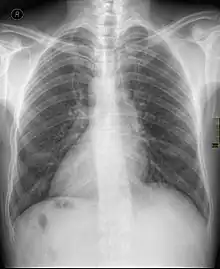

Dextrocardie

Cœur normal

La dextrocardie est une malformation de naissance dans laquelle le cœur se trouve dans la moitié droite du thorax. La pointe du cœur est aussi orientée à droite.